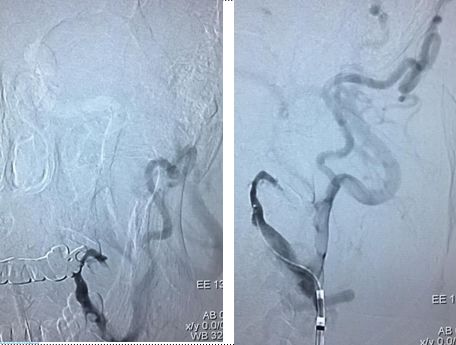

在颈内远端用6*30Solitaire逐次向近端释放支架(夹层可能性大)

支架释放状态血管通畅,逐渐找到血管闭塞部位

支架在病变最近端释放

11-3,21:40:血管再通,支架释放解脱

右椎V4段狭窄,2.5*15球囊扩张(应用替罗非班)

13:40:应用3.0*13Apollo支架释放血管再通